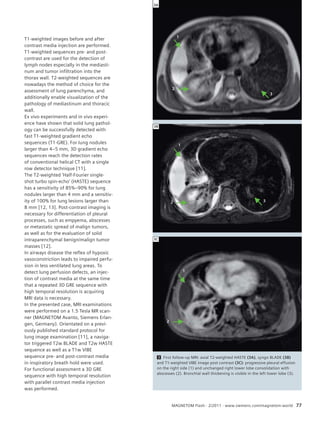

MRI of the Lung

74 Case Report: MRI of the Lung

in a Young Child with Abscess

Pneumonia Caused by H1N1

Infection

Monika Eichinger, et al.